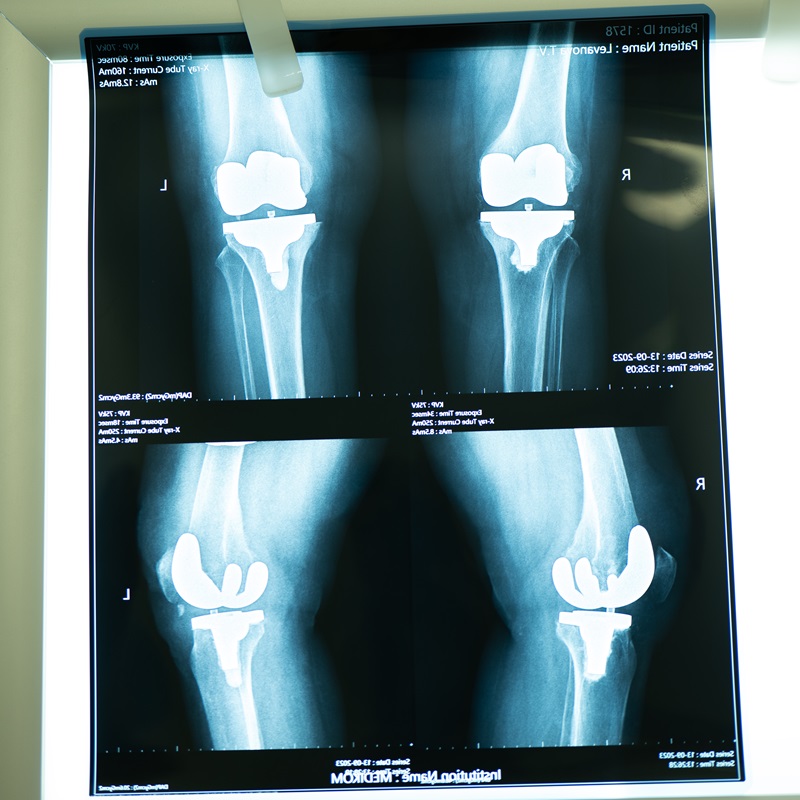

Ендопротезування колінного суглоба в Києві

Сучасні операції з артропластики — заміни суглобів на штучні ендопротези — рятують пацієнтів від інвалідізації. Провести ендопротезування колінного суглоба в Києві можна у клініці МЕДІКОМ, лікарі якої мають багаторічний досвід та найякісніше обладнання для таких хірургічних втручань.

Ендопротезування колінного суглоба — це заміна його пошкоджених природних частин на штучний ендопротез. Не завжди є потреба у тотальному ендопротезуванні, при якому замінюються всі суглобові компоненти. У частині випадків достатньо часткової заміни, якщо решта структур суглоба можуть надалі виконувати свої функції. Це визначається під час діагностики, рішення про вибір методу приймає лікар.

Під час хірургічного втручання застосовується загальний наркоз. Всі ушкоджені частини суглоба видаляються, замість них встановлюється імплант. Фіксація ендопротеза відбувається за допомогою цементу або без нього. Встановлюється дренаж, накладаються шви чи скоби та стерильна пов’язка.